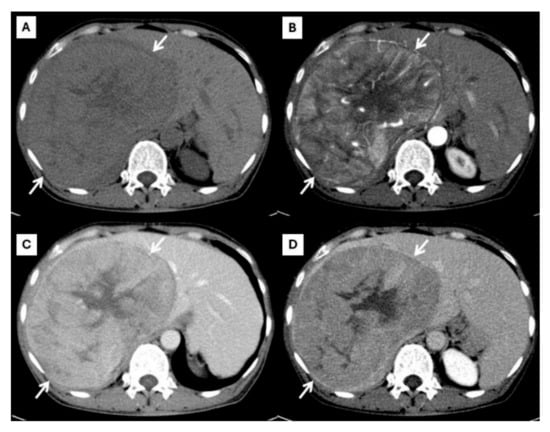

| Later arterial phase | Arterial phase hyperenhancement | Rim-like enhancement |

| Portavenous phase | Non-peripheral washout | Progressive peripheral enhancement |

| Delayed phase | Capsule enhancement | Progressive peripheral enhancement |